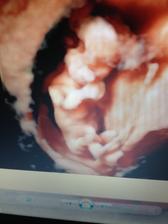

autor@nikuskanaj87 tak ono sa podarilo velmi rychlo,az 2x len bohuzial v oktobri minuleho roka som o mimi prisla,tak verim ze tentoraz sa dockam vonaveho babetka v decembri☺️dakujeeem